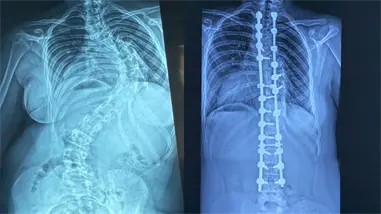

Landrón detalló que, entre los pacientes recibidos, se atendieron casos de trauma craneoencefálico severo, lesiones vértebro-medulares graves y fracturas abiertas de muy alta energía, sin que se produjeran defunciones.